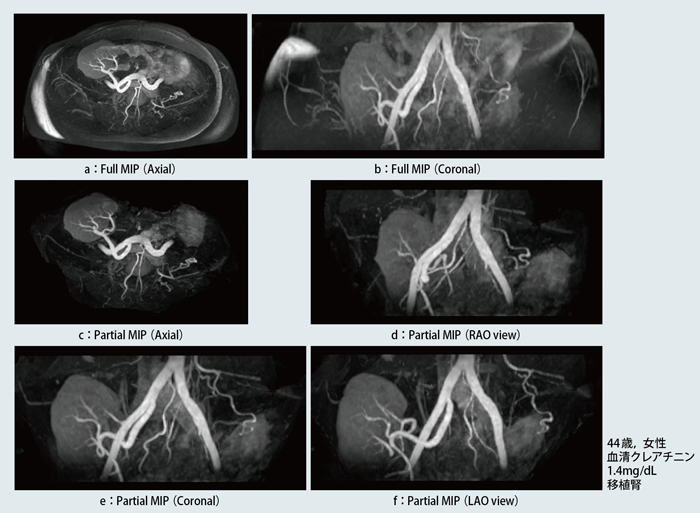

症例2は,44歳,女性で,生体腎移植後に血清クレアチニン値が1.4mg/dLとやや高値を示したので,腎動脈狭窄の有無を調べるためMRAを施行した。骨盤部の動脈でも,TI 2200msと長めに設定した方が末梢動脈の描出能が向上することが経験的にわかっている。Full MIPでは,静脈がほぼ完全に抑制され(図4 a,b),体表の脂肪信号をカットするだけで,MIP画像が作成可能である(図4 c〜f)。

図4 症例2:移植腎動脈狭窄疑い